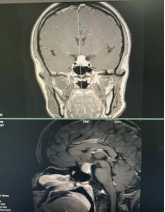

时间回到9月,李婆婆突然发现近两天看东西重影,视力下降得厉害,急忙赶到医院就诊。检查结果让一家人揪紧了心——她患上了垂体大腺瘤伴卒中可能。肿瘤不仅压迫视神经,还紧贴颈内动脉。李婆婆患有高血压,更增加了手术难度和风险,就像在“血管旁拆弹”。

面对这一复杂病例,神经外科与手术麻醉科、医学影像科、内分泌科等多学科团队进行了全面讨论,还专门邀请华西医院神经外科贺教江教授会诊。在征求患者及家属治疗意愿后,团队最终敲定了“神经内镜下经鼻蝶窦切除术”这一微创方案——从鼻腔自然通道入手,避开开颅的大创伤。术前,团队对患者各项基础疾病进行了控制,并制定了详细的术后康复和长期随访方案。手术麻醉团队也制定了周密预案,以保术中生命体征平稳。

手术当日,在贺教江教授指导下,神经外科医生团队利用高清神经内镜系统提供的放大视野,清晰分辨了肿瘤、神经和血管结构,成功避开颈内动脉等重要结构,精准剥离了肿瘤,同时对视神经进行了充分减压,只用了90分钟就完成了手术。术后查房发现,患者视力较术前明显改善。